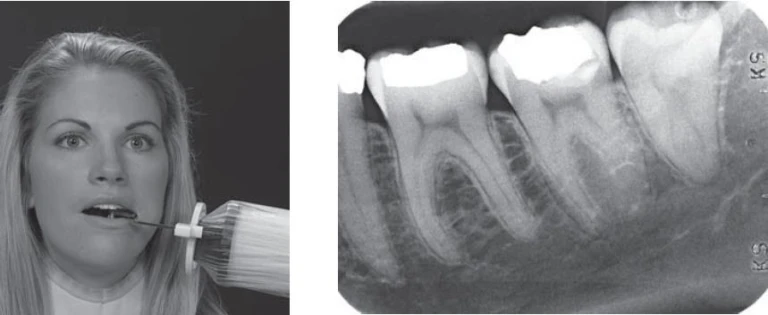

Đọc tiếp1. Bệnh nhân nam 39 tuổi tới khám vì lý do cắn vỡ một phần răng 47 có nhu cầu…